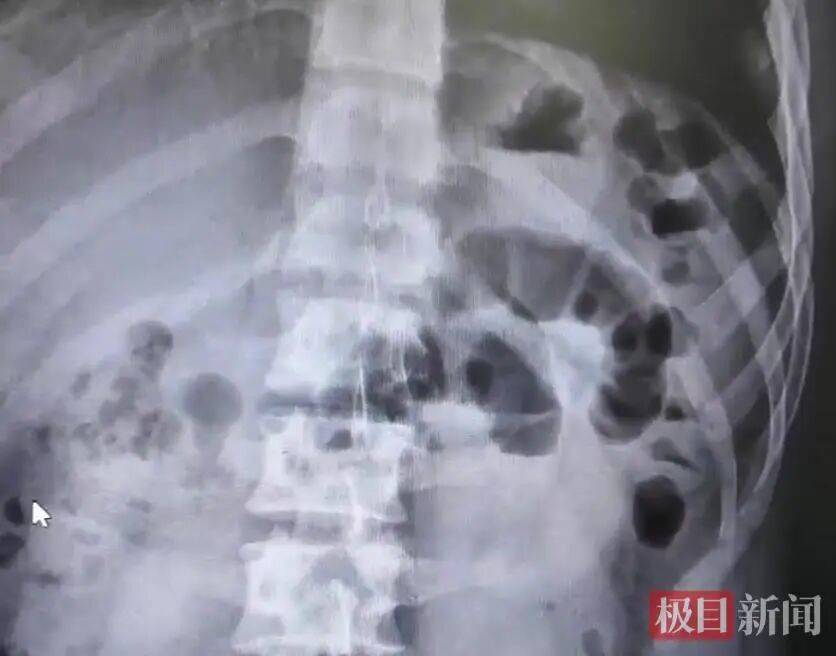

CT检(jian)查(受访者(zhe)供图)

经过腹部CT检(jian)查,李阳被确诊为典型小肠梗阻,病因正是(shi)短时间内过量进食胡萝卜,肠道堵塞。